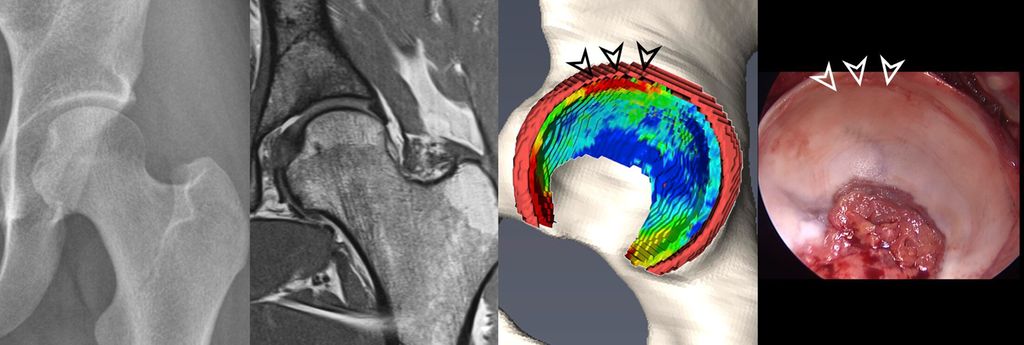

Fig. 1: Traction MR arthrography allows for better visualization of the opposing acetabular and

To improve visualization of the central joint cavity during MR arthrography, axial leg traction can be applied, similar to the joint distraction needed during hip arthroscopy (Fig. 1). Traction MR arthrography of the hip has shown high accuracy in detecting chondrolabral lesions, ligamentum teres injuries, and intra-articular loose bodies and has demonstrated its value in predicting failure of FAI surgery.5–8 It is particularly helpful for better visualizing the extent of cartilage damage in older patients with mild radiographic joint degeneration and thus aid in surgical decision making. Traction MR arthrography can also detect unstable labral tears in patients with hip dysplasia and may aid in planning treatment for femoral head necrosis in young patients with early collapse and preserved joint space.4

Fig. 2: 3D models of hip cartilage and labrum with color-coded dGEMRIC indices to visualize biochemical cartilage degeneration (red color, black arrowheads) which was confirmed during surgery (white arrowheads).

More recently, we introduced a deep-learning-based approach for automatic segmentation of hip cartilage and labrum using a 3D dGEMRIC sequence (MP2RAGE). The approach allows for automatic and reliable generation of 3D models of hip cartilage and labrum within seconds, and providing both 3D morphologic information of the hip joint as well as color-coded dGEMRIC indices for quantitative analysis of cartilage damage (Fig. 2 & 3).19